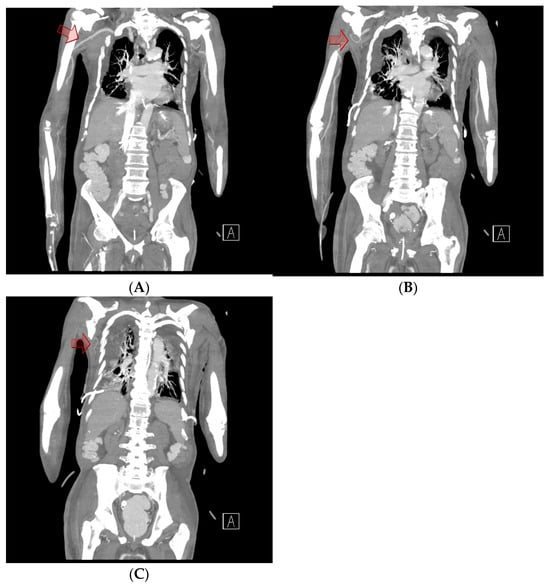

Figure 1. Chest computed tomography. (A) Sagittal view showing the formation of a hematoma measuring approximately 19 × 8 cm. (B) Axial view showing a newly formed 13 × 10 cm hematoma in the right upper anterior chest wall without evidence of active bleeding or pseudoaneurysm.

Chest computed tomography (CT) angiography revealed a newly formed 18.7 × 13.1 × 9.6 cm hematoma in the right upper anterior chest wall, with no signs of active bleeding or evidence of a pseudoaneurysm or malignant tumor (Figure 1 and Figure 2). On the fourth day post-onset, transarterial angiography was conducted via the right common femoral artery. Angiograms of the right subclavian artery, right internal mammary artery, and thoracic aorta showed no active bleeding, precluding the possibility of embolization. To manage the resulting anemia, 2 units of PRCs were transfused.